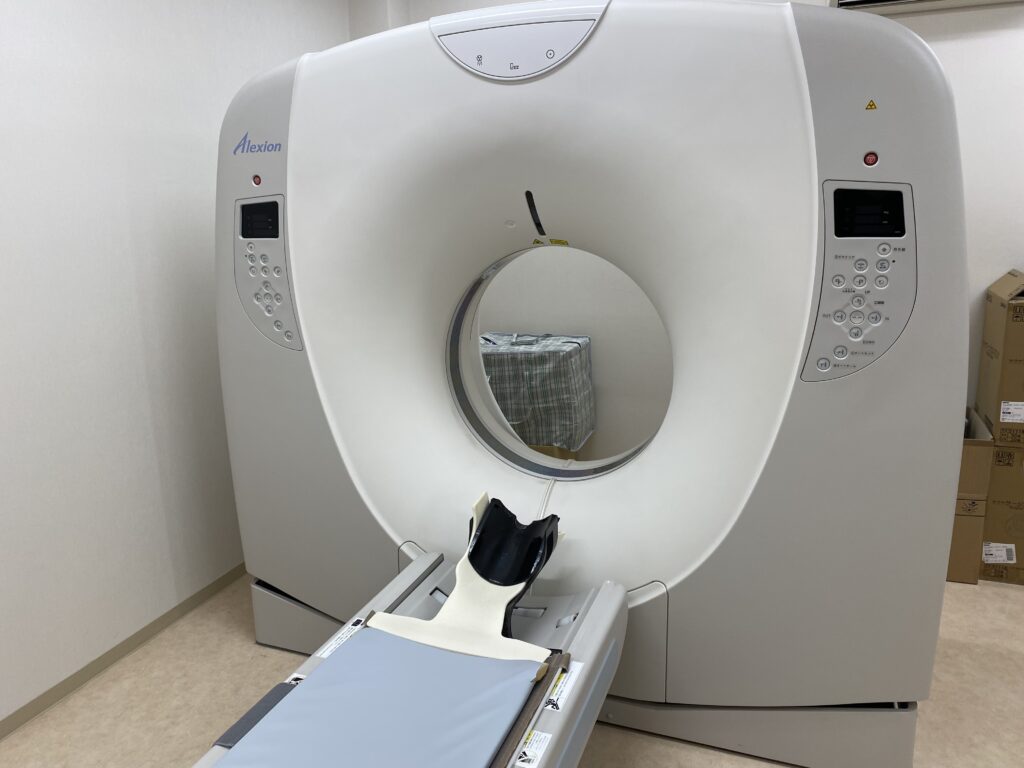

PythonでDICOMビューアを作ろう 第5回・前編 冠状面・矢状面も差分表示対応!2Dビューアの完成へシェル君。

ヘリカルCTは横断面だけではなく矢状面や冠状面も作ることができます!ふかつ泌尿器科・皮ふ科クリニック。